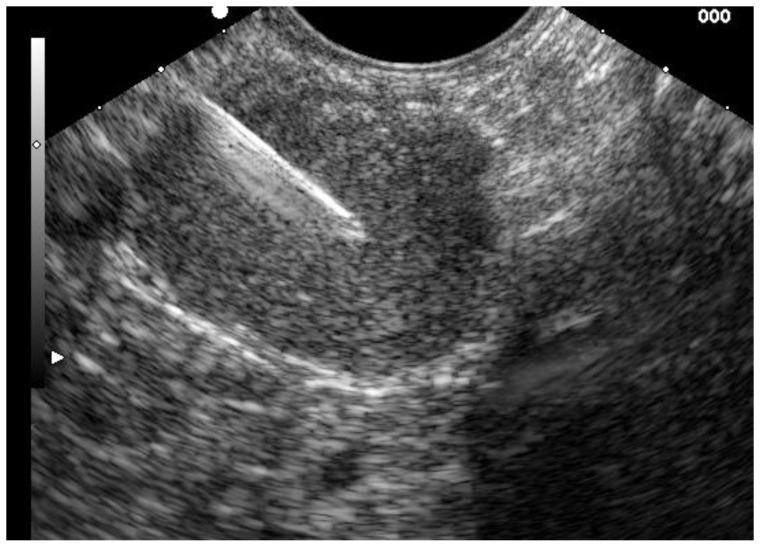

Biliary diseases are common, but clinical symptoms are often unspecific and direct access and visualization of the biliopancreatic system for diagnostic purpose is difficult. In the last decades endoscopic ultrasound (EUS) has become a primary method in the gastrointestinal tract. It significantly changed the role of endoscopy in diagnostic imaging in the gastrointestinal tract and adjacent organs. EUS has become an effective diagnostic tool in biliary stone disease as well as in the diagnosis of indeterminate biliary strictures. Furthermore, an EUS-directed transmural approach emerged as a safe and effective alternative to ERCP in patients requiring biliary drainage, in particular as a backup method if standard ERCP-approach fails. Development of new techniques, specific accessories and stents during the last decade led to an enormous step forward in terms of efficacy and safety of an EUS-directed approach. In the current article technical and clinical aspects of EUS-guided diagnostic and therapeutic approaches in different clinical indications will be discussed together with a review of the available data.

胆道疾病很常见,但临床症状往往不具特异性,且为诊断目的直接进入和可视化胆胰系统很困难。在过去几十年中,内镜超声(EUS)已成为胃肠道的主要检查方法。它显著改变了内镜在胃肠道及邻近器官诊断成像中的作用。EUS已成为胆石症以及不明原因胆管狭窄诊断的有效工具。此外,在需要胆道引流的患者中,EUS引导的经壁入路已成为一种安全有效的替代内镜逆行胰胆管造影(ERCP)的方法,特别是在标准ERCP方法失败时作为备用方法。过去十年中新技术、特定附件和支架的发展,在EUS引导方法的有效性和安全性方面取得了巨大进展。在本文中,将讨论EUS引导的诊断和治疗方法在不同临床适应症中的技术和临床方面,并对现有数据进行综述。